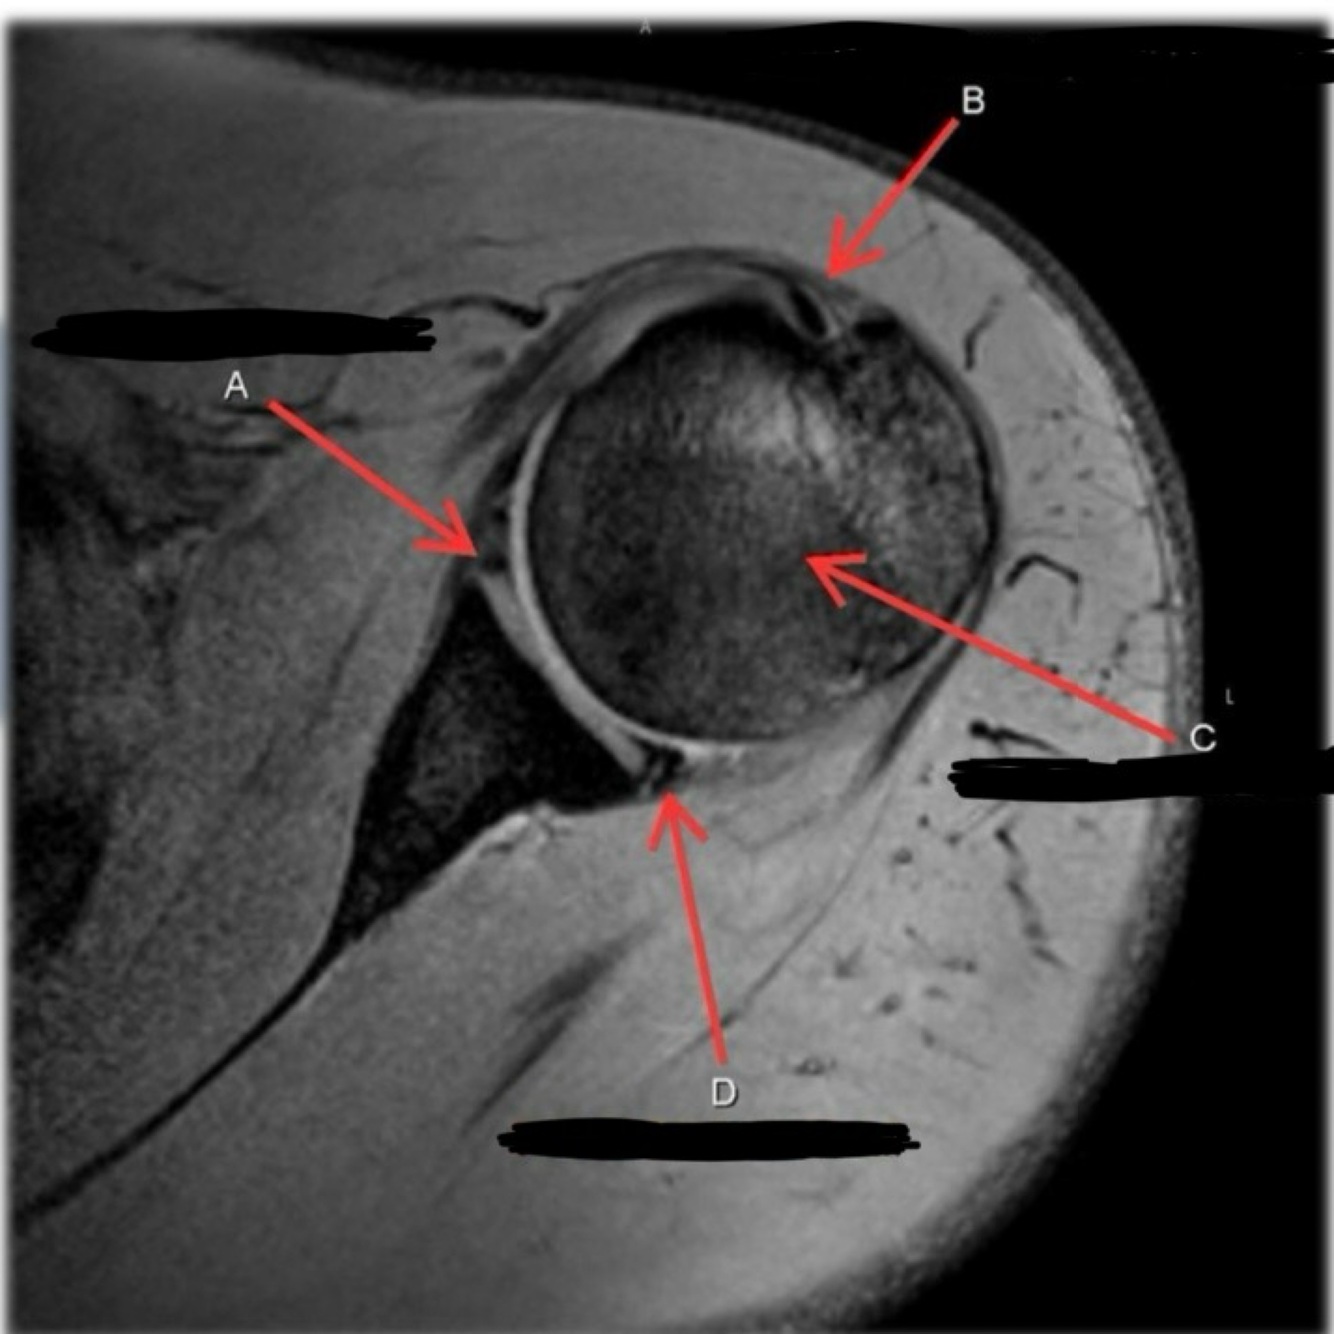

What is letter A?

SUBSCAPULARIS MUSCLE

Q

A

What is letter C?

INFRASPINATUS MUSCLE

What is letter D?

GLENOID